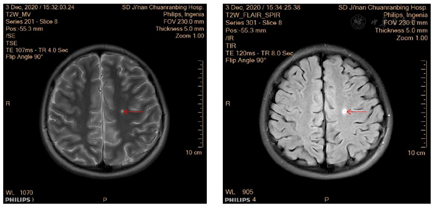

影像学检查:2例患者均行磁共振成像(MRI)检查,MRI示双侧半卵圆中心见小片状长T1长T2异常信号,FLAIR呈高信号(图B箭头),DWI呈高信号,ADC图低信号(图2)。

注:双侧半卵圆孔中心见小片状长T1长T2异常信号(图A箭头),FLAIR呈高信号(图B箭头),DWI呈高信号,ADC图低信号。